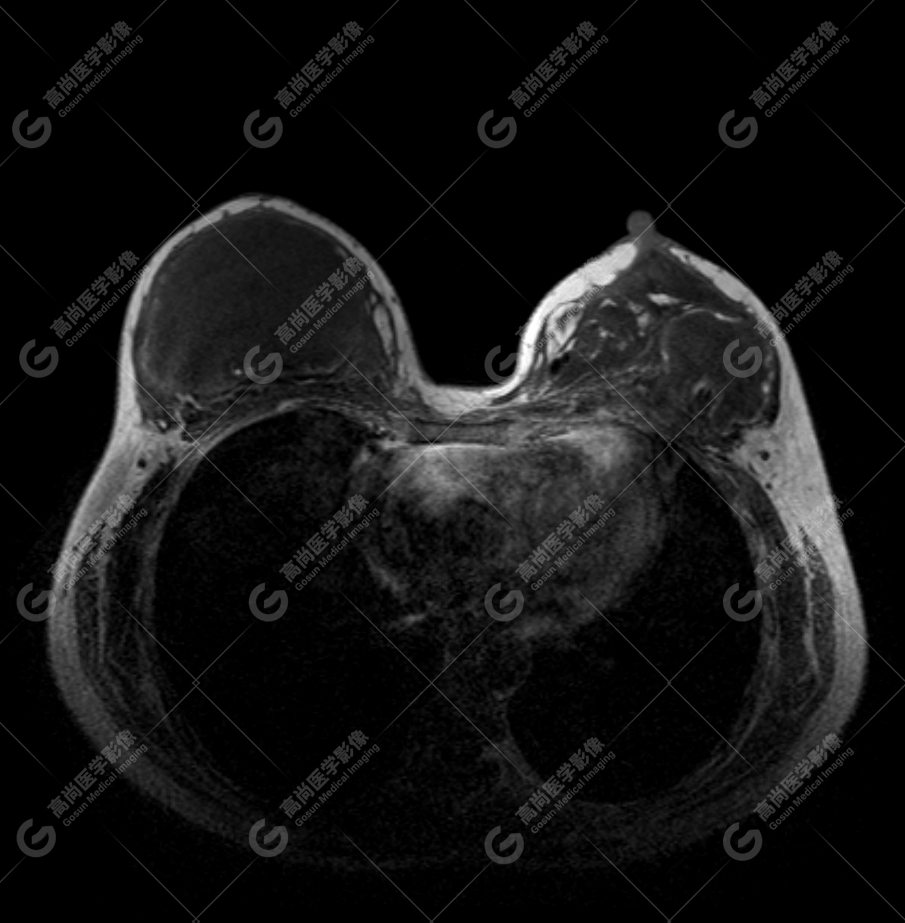

病例 2:乳腺假体植入术后约 1 年

双侧假体内包膜可见多发皱褶影,提示包膜趋向挛缩。